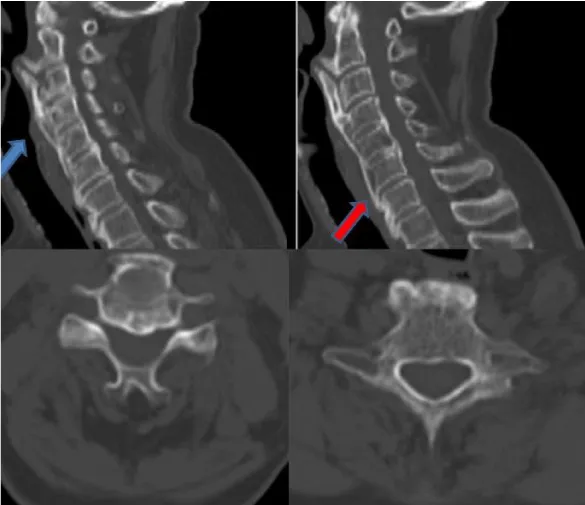

A 65- year old male patient with history of diabetes mellitus was admitted to our outpatient clinic with neck pain, dysphagia and sleep apnea for over 5 months. Previously evaluated by the otolaryngology department a esophagography a slight compression of the upper cervical esophagus segment was observed. He stated that he lost 6kg in 6months due to the dysphagia. On his cervical CT scan revealed broad ossification of the anterior longitudinal ligament from C2 to T1 with anteriorly beaking osteophytes surrounding the vertebral bodies causing compression of the trachea and esophagus on C2 and C3 (Figure 1). Magnetic Resonance Imaging (MRI) showed that there were no disc pathologies; vertebral heights and spinal alimentation were normal. The spinal canal and spinal cord were intact. (Figure 2). With the diagnosis of DISH, the patient underwent surgery. With an anterolateral approach the ossified pathological segment was removed with a high-speed drill and no compression of the surrounding soft tissue fractures were confirmed. The patient’s symptoms revealed immediately after the surgery and on the postoperative control CT scan, total clearance of the ossified structures were observed (Figure 3).

The fact that makes our case unique is the multiple cervical vertebra involvement of DISH starting in the upper cervical vertebra which has not been reported in the literature in this variety before. Forestier disease, being more common in the thoracic and lower cervical area, show a vertical growing pattern in the thoracic and horizontal pattern in the cervical area. In our patient the ossification mimicking a bird’s beak had vertical growing characteristics despite being in the upper cervical area. Also, multi-level involvement in the cervical spine is rare because the cervical vertebrae are more mobile than the ones in the thoracic area. In our patient ossification from C2 to T1 was present which has not been presented in the literature before. Rapid improvement of the patient’s symptoms confirmed with the radiological images strenghten the hypothesis that patients with dysphagia, especially in the ones with weight loss due to it, have better outcomes when approached surgically than conservatively. In our opinion, it is not necessary to remove all the ossificated levels. In our case, we just drilled the segment in contact with the esophagus and trachea and had excellent results.